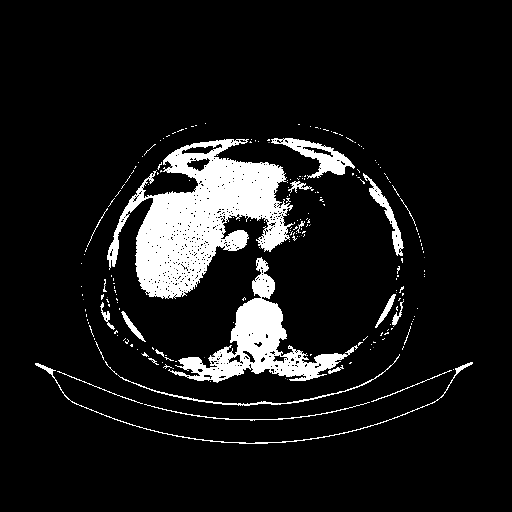

Reconstructed NATIVE CT scan (cycle consistency)

Full window (WL 1023.5, WW 4095 β†’ Low βˆ’1024, High +3071)

Actual HU range: [-1024.0, 3071.0]